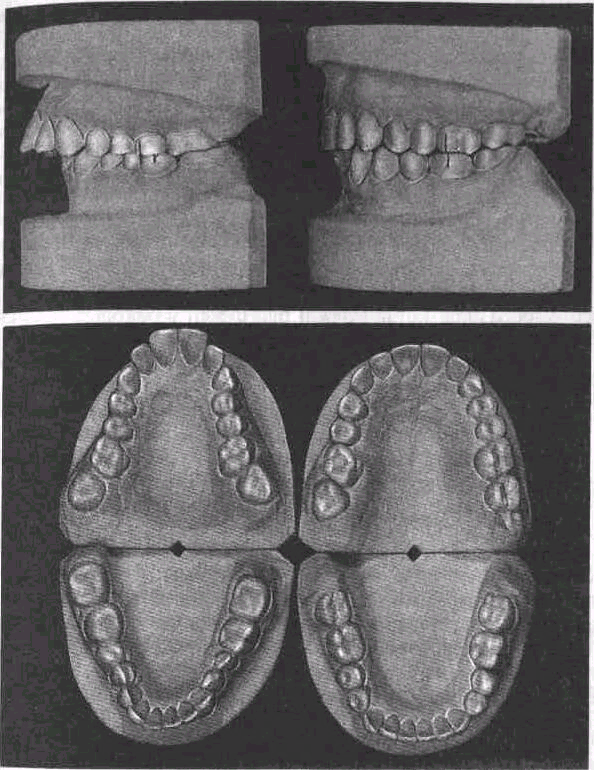

Раздел: Фотопутеводитель